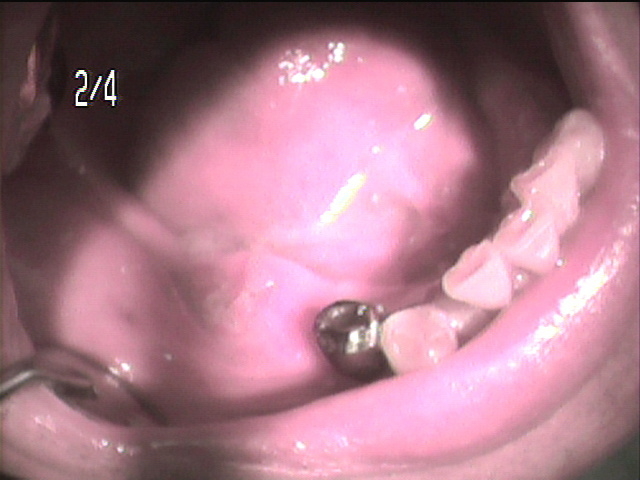

刈谷市半城土町よりお越しの 80歳女性の Iさんは、 毎月入れ歯と自分の歯をメンテナンスに通院されています。

刈谷市半城土町よりお越しの 80歳女性の Iさんは、 毎月入れ歯と自分の歯をメンテナンスに通院されています。